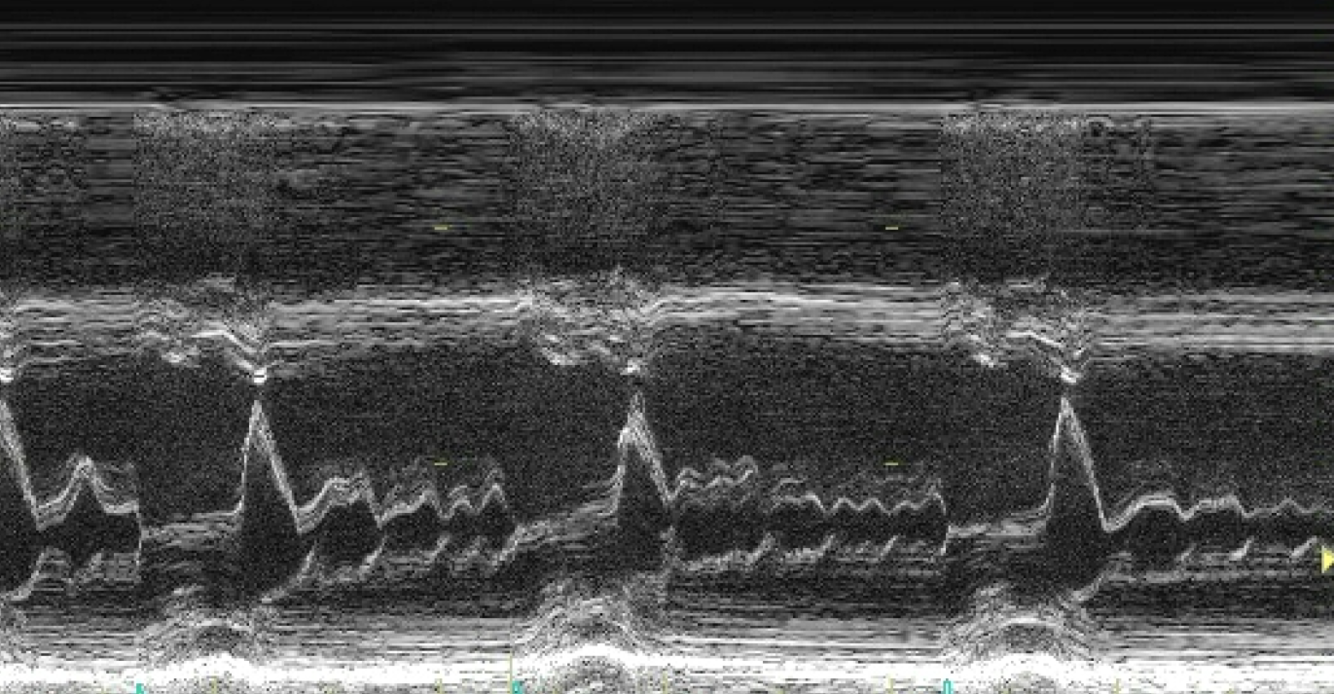

Diagnosis?

SAM

name 2 factors that make gradient worse in SAM

1) Earlier time to onset of septal contact by MV

2) Duration of SAM-Septal contact